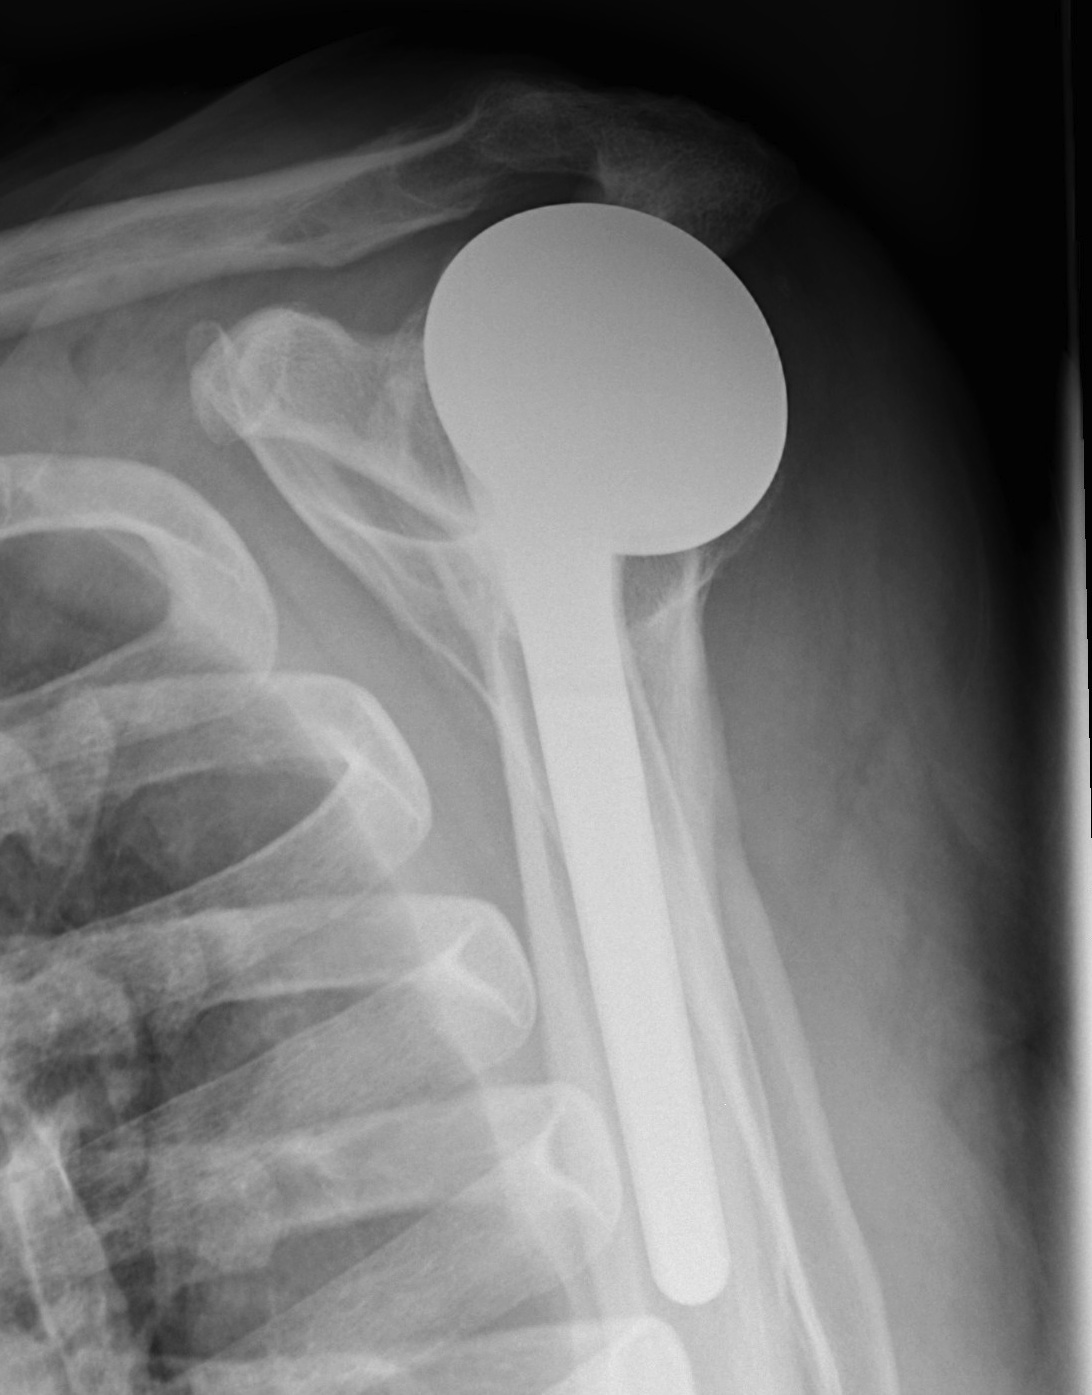

Arthroplasty

Indications

Acute unreconstructable fracture > 60